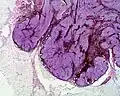

A blue nevus is a type of coloured mole, typically a single well-defined blue-black bump.[1][2]

The blue colour is caused by the pigment being deep in the skin.[4]

• A cellular blue nevus is a cutaneous condition characterized by large, firm, blue or blue-black nodules.[7]: 701